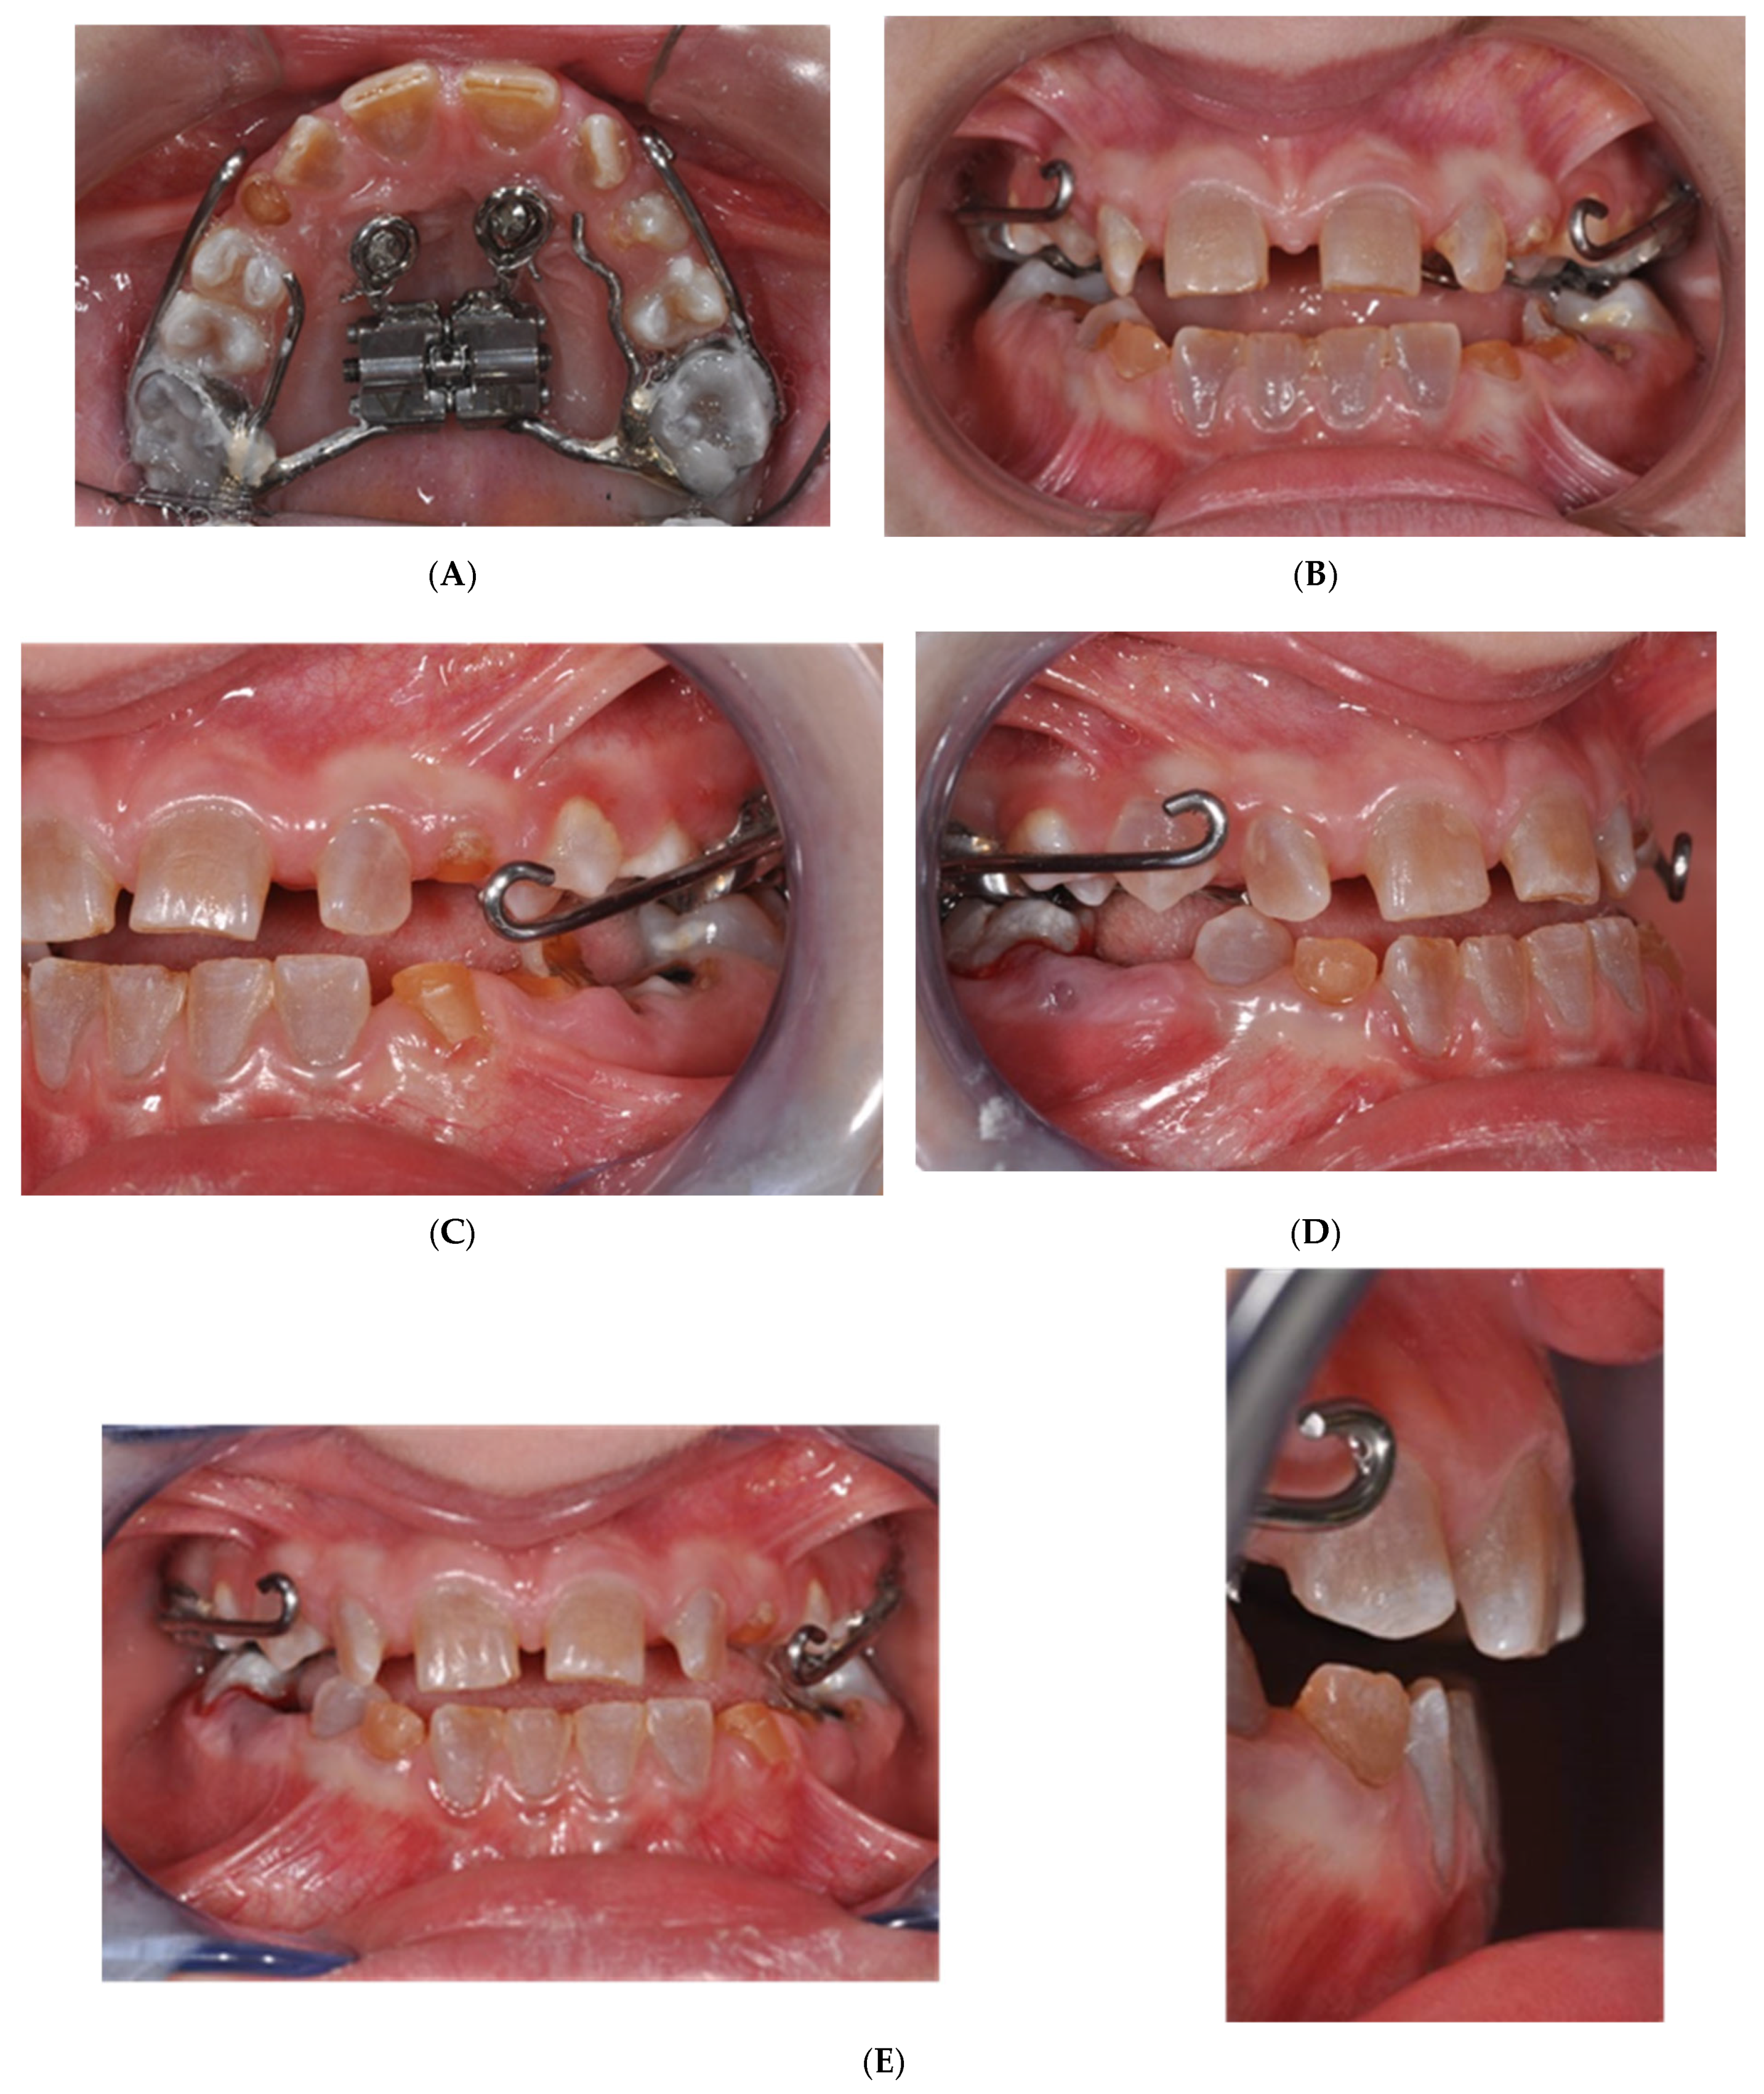

2.2. MSE Treatment in Patients with Osteogenesis Imperfecta and Dentinogenesis Imperfecta